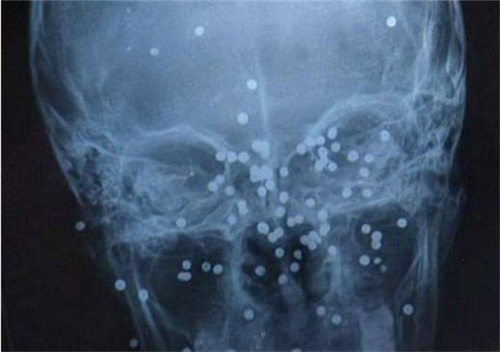

ប្លែកៗ ៖ Zhang Qin គឺជាក្មេងស្រីវ័យ ១២ ឆ្នាំ មកពីភារតី ប្រទេសចិន ត្រូវបានភ្នាក់ងារសារព័ត៌មានចិន chinadaily បញ្ជាក់អោយដឹងថា នៅលើផ្ទៃមុខរបស់នាង បានបន្សល់ទុកនូវស្មាមជាំខ្មៅតូចៗ ដល់ទៅ ៦៨ បន្ទាប់ពីនាងត្រូវបានប្អូនប្រុសវ័យ ១១ ឆ្នាំ យកកាំភ្លើងបាញ់មកលើផ្ទៃមុខរបស់នាងដោយអចេតនា ខណៈពេលដែលពួកគេកំពុងតែប្រឡែងលេងជាមួយនឹងគ្នា។

លើសនេះទៅទៀត របាយការណ៍ដដែលក៏បានបញ្ជាក់បន្ថែម អោយដឹងផងដែរថា ភ្លាមៗនោះជនរងគ្រោះក៏ត្រូវបានបញ្ជូនទៅកាន់មន្ទីរពេទ្យ ដើម្បីសង្គ្រោះបន្ទាន់ តែជាសំណាងល្អ វាមិនបានប៉ះពាល់ដល់អាយុជីវិតនោះទេ។ រយៈពេល ៣ ខែក្រោយ គេក៏បានរកឃើញថានៅលើផ្ទៃមុខរបស់នាងបែរជាចាប់ផ្តើមលេចចេញនូវស្នាមជាំខ្មៅតូចៗទៅវិញ បន្ទាប់ពីបានកើតមានឡើងនូវឧបទ្ទេវហេតុចៃដន្យមួយនោះ៕